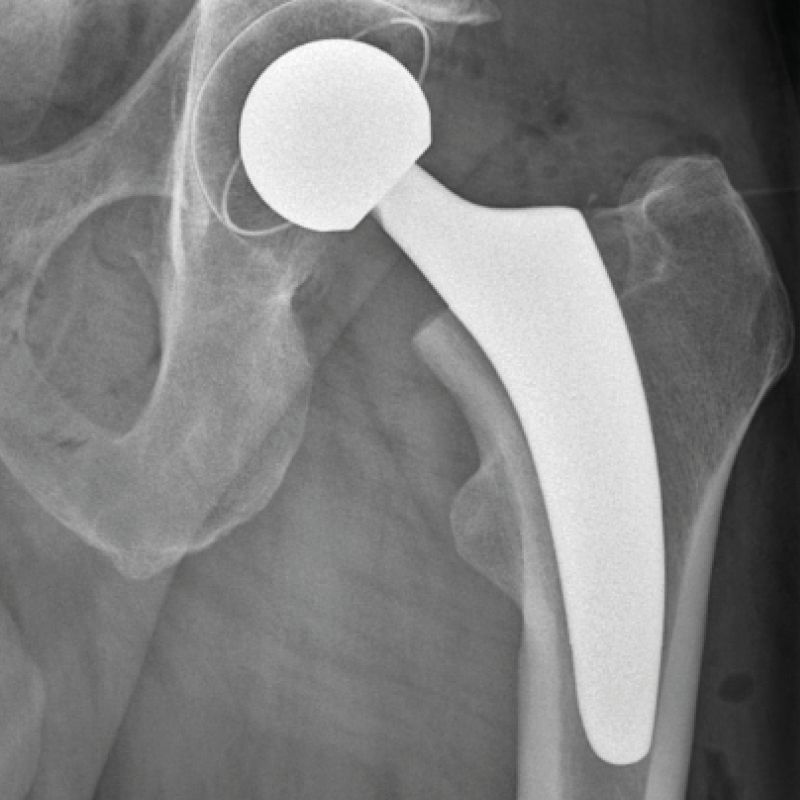

Röntgenaufnahme eines Hüftgelenks mit eingesetzter Hüftprothese.